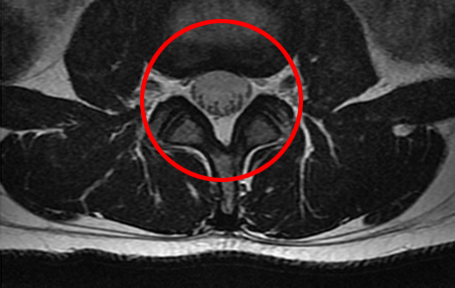

• 모커리한방병원 MRI로 본 정상적인 척추관 이미지

정상적인 척추관